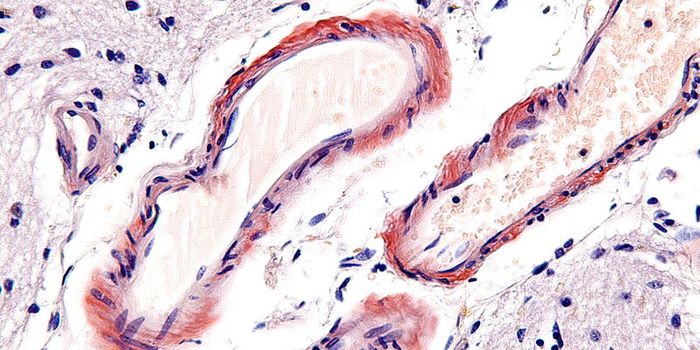

JAN 07, 2022CancerThe blood-brain barrier (BBB) describes the complex vasculature network that delivers oxygen and nutrients to the brain. ...